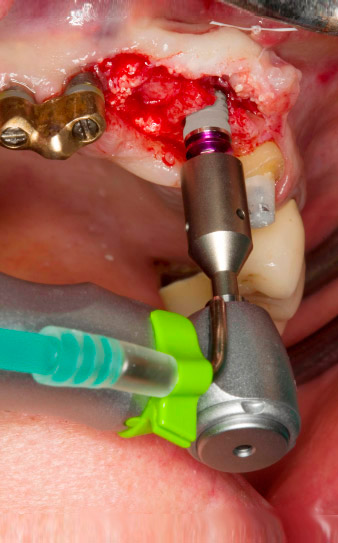

Tapping with the WS-75 L contra-angle handpiece

Fig. 3: Tapping with the WS-75 L contra-angle handpiece at a ratio of 20:1 (programme P4). Implantmed’s high torque, the hexagon chucking system for reliable power transmission and the automatic reversal of the direction of rotation when resistance gets too high prove particularly helpful here.

Motorized placement of the implant

Fig. 4: Motorized placement of the implant with the WS-75 L contra-angle handpiece at a ratio of 20:1 (programme P5).